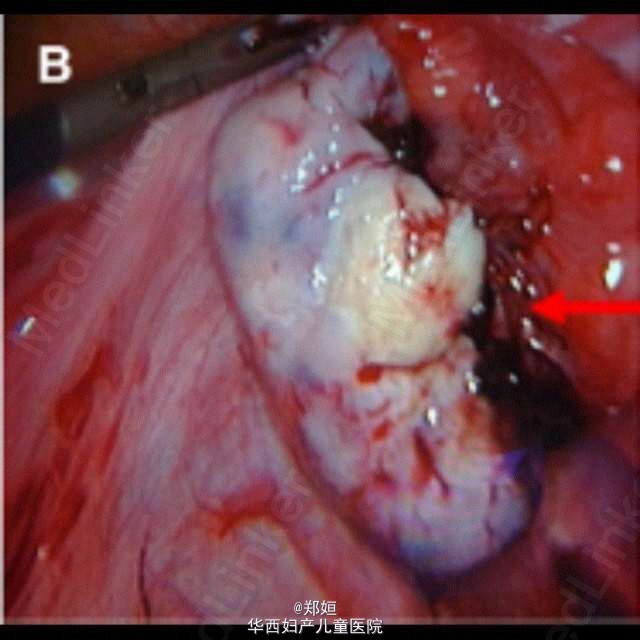

最近看的一个病例,给大家分享。 27岁女性,因出现幻觉入院。 既往:10天前出现流感样病症。 神经科检查示患者有顺行性遗忘症状和行动障碍,格拉斯哥昏迷评分从10分降到6分,全身CT检查示右侧卵巢有直径4cm的囊性包块。